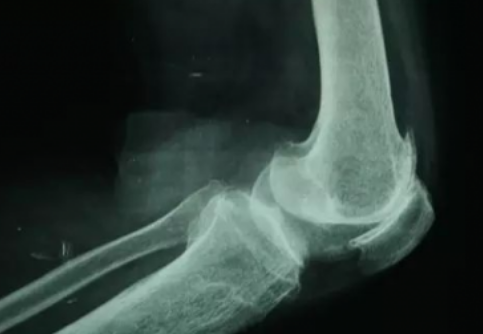

膝关节是人体运动量最多,负重量最大的关节之一。由于全民运动的倡导,有时过度的运动和不恰当的生活习惯不但不能保护膝关节,往往适得其反。

当今最流行的运动莫过于步行,但是过量的步行一样会损害膝关节,膝关节退变类似于机械磨损,过量的步行最终都将导致骨性关节炎发生。据一项步行与膝关节骨性关节炎研究显示,健康的步行建议:40周岁以下每日步行控制在1万5千步以内,60周岁以上每日步行控制在6000步以内,本人认为以上步数是一个参考,步行既然是运动就得循序渐进的规律,要量力而行,如果从没步行过2000步一天的人突然步行1万步,不管你膝关节再好也会出问题,我不否认运动促进健康但更认同循序渐进的运动和锻炼。如果你想健康的步行运动,建议你平常步行的次数上每日加上3-500步,达到上述参考数据来保护自己的膝关节。一个是注意控制运动量,如果感觉膝盖疼痛就要休息。另外,很重要的一点,我们想膝关节不受伤怎么办?不是靠护具去保护,而是靠肌肉去保护。运动锻炼达到关节周围肌肉的强壮,发达的肌肉反过来又对关节起保护作用。平时多练肌肉力量,另外还有你的反应性、敏感性等等,这些都对关节的保护极其重要。当然,也要学会注意休息,练得太多也不好。

步行运动是给我们的业余生活增加乐趣和健康的一种非常好的方式,但千万不要“本末倒置”。如果出现膝关节疼痛不适或肿胀,都应该到医院找专业的运动医学医生或者骨关节科的医生看病,需要治疗的早治疗,以免耽误。